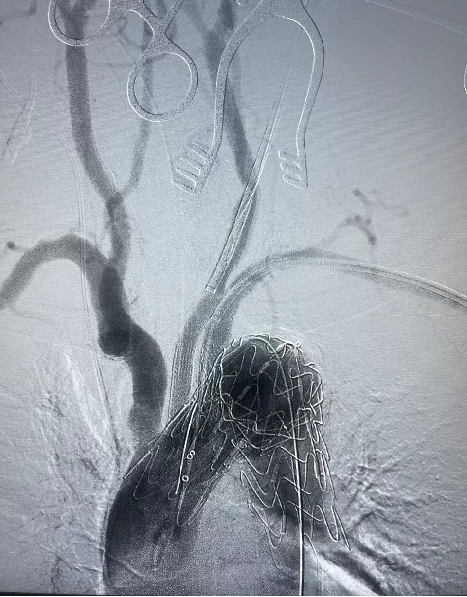

术后实时造影

6个月随访

A、D、G为整体图,其中A为分支支架、D为主支架和分支支架衔接处、G为主支架,B、C、E、F、H、I分别为A、D、G方框处的局部放大图